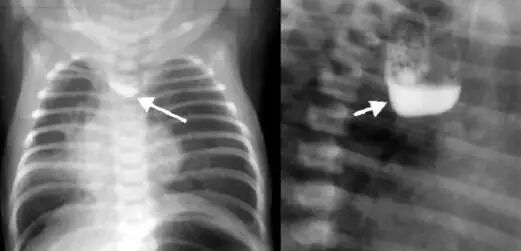

基于干细胞的器官移植治疗新生儿食管闭锁

先天性食管闭锁是危及生命的严重畸形,可在胎儿20周时进行早期诊断,主要表现为食道上段与胃部不连,使人难以下咽,从而导致窒息和肺炎等其他严重的问题。根据国内统计,我国食管闭锁的发生率为1:(2000~4500),占消化道发育畸形的第三位[2]。今年4月,英国媒体报道称,英国医生将利用干细胞疗法来治疗新生儿食管闭锁,这也是全球的首次尝试[3]。

早在几年前,该研究团队就曾为11岁的严重气管缺陷男孩实施了干细胞移植,这也是全球首例干细胞移植治疗气管缺陷。研究人员用患者自身的干细胞诱导培养成气管组织,并移植至患者身上,以让他更容易呼吸。2年后,《柳叶刀》杂志报道了该案例的后续跟踪结果,移植的器官并未在患者身上发生排斥反应,这名少年已经能够正常生活,并且不需要任何的抗排斥治疗[4]。《柳叶刀》杂志呼吁开展更多的研究,以加速移植器官结构刚度的形成以及增加移植器官的可用性和有效性。